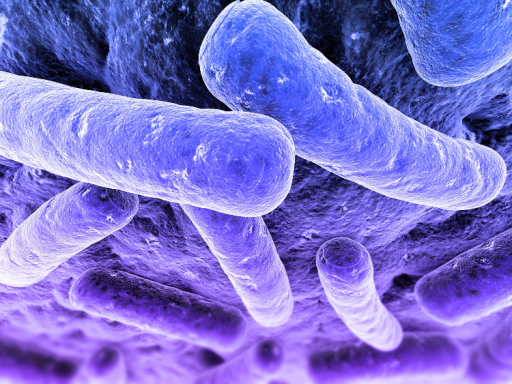

Фотографии бактерий, вызывающих бактериальные пневмонии у животных